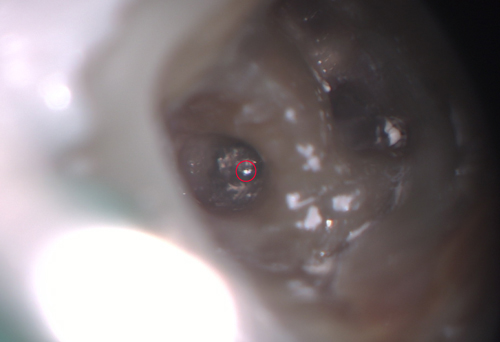

隔壁を作ってある程度洗浄したところです。なんとも変な根管系のように見えましたが赤丸の中は前医が除去し切れていないファイバーポストでした。

除去したところ。

これで破折ファイルの頭が見えてきました。それにしても暴力的に根管を削ってあります。歯の治療は内側も外側も最小限の切削で最大の効果が得られるようにすることが重要です。再治療になることは必ずと言って良いほどあるわけで、その際に残っている歯質の量が多いか少ないかは決定的に予後を左右します。